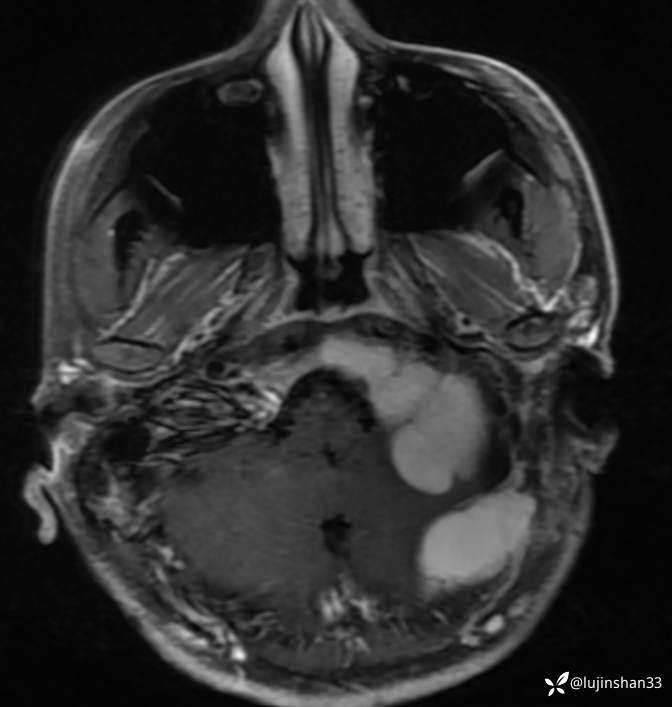

半年后复查

术后1年半复查CT及MRI